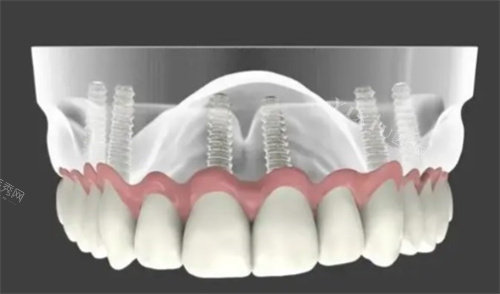

高难度种植:主导完成惠安首例“ALL-ON-4全口即刻负重”手术,患者术后4小时进食软食。

“68岁张爷爷全口缺牙,多家医院建议传统活动假牙,王院长用4颗种植体撑起全口牙冠,当天啃苹果!”

方案:ALL-ON-6全口种植+即刻负重

“以前戴活动假牙吃饭总硌牙龈,王院长给我种了6颗牙,当天就能啃排骨!护士还手把手教我清洁种植牙,现在吃饭香、说话清,邻居都说我年轻了10岁!”